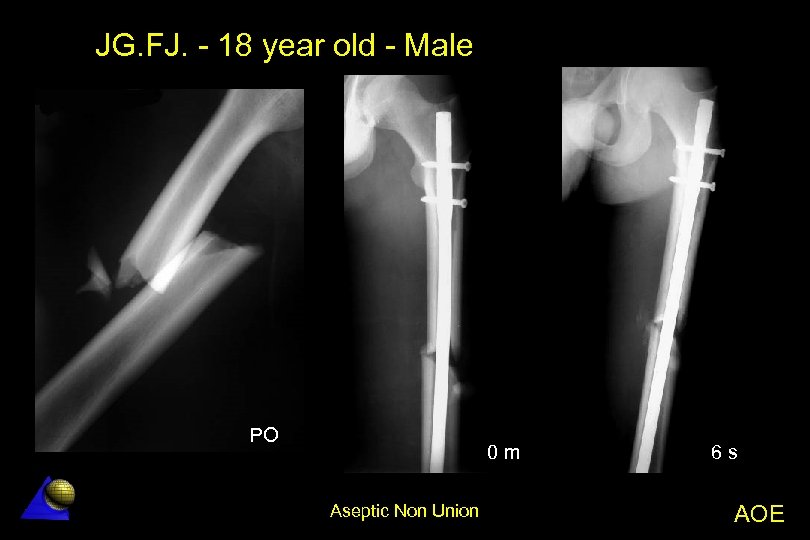

JG. FJ. - 18 year old - Male Motorcycle accident - 5. 5. 02 l l Left femur B 2. 2 fracture Operation: 6. 5. 02 â l l 9. 02 - Small wedge resorption and instability 25. 11. 02 Operation â â l l UFN locked nailing with satisfactory reduction Decorticatión and LCP fixation without nail removal Bone grafting Bone healing in 4 months (10 months since the accident) Complete function at 12 months. Aseptic Non Union AOE

JG. FJ. - 18 year old - Male PO 0 m Aseptic Non Union 6 s AOE

JG. FJ. - 18 year old - Male 4 m 6 m Aseptic Non Union AOE

JG. FJ. - 18 year old - Male 6 m 7 m Aseptic Non Union AOE

JG. FJ. - 18 year old - Male 10 m 12 m Aseptic Non Union AOE

JG. FJ. - 18 year old - Male 15 m Aseptic Non Union AOE